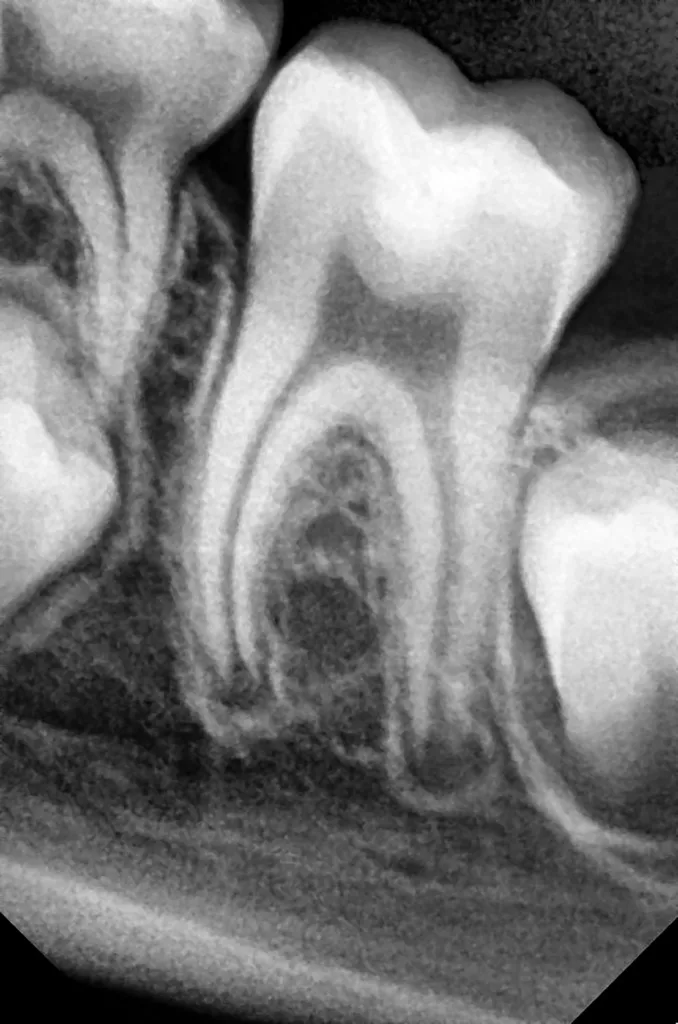

V. Slabkovskyi, O. LiutikovJahr vor dem Durchbruch des Zahnes 36.

Das fünfjährige Mädchen stellte sich 2017 zur jährlichen Routinekontrolle vor. Im Rahmen der Untersuchung wurden Röntgenaufnahmen der Milchmolaren gemacht (Abb. 2). Der klinische und radiologische Befund der vor uns früher gelegten Kompositfüllungen war gut, es wurde allerdings eine PEIR an den noch nicht durchgebrochenen ersten bleibenden Molaren festgestellt (Abb. 2). Den Eltern wurde empfohlen, sich unverzüglich bei Beginn des Durchbruchs der ersten Molaren erneut zur Behandlung vorzustellen. Ein Jahr später erschien die junge Patientin schmerzfrei zur Kontrolle. Der Zahn 36 war noch teilweise mit Gingiva bedeckt. Auf einer neuen Röntgenaufnahme (Abb. 1) wurde die PEIR-Läsion mit unveränderter Größe in pulpanahen Bereichen bestätigt (Grad 3 der Läsion nach Seow). Der Zahnschmelz sah intakt aus, es konnte kein pathologischer periapikaler Befund bei den noch nicht ausgewachsenen Zahnwurzeln festgestellt werden. Daraufhin wurden die verschiedenen Behandlungsmöglichkeiten von Fissurenversiegelung bis Vitalerhaltung der Zahnpulpa mit den Eltern des Kindes besprochen.